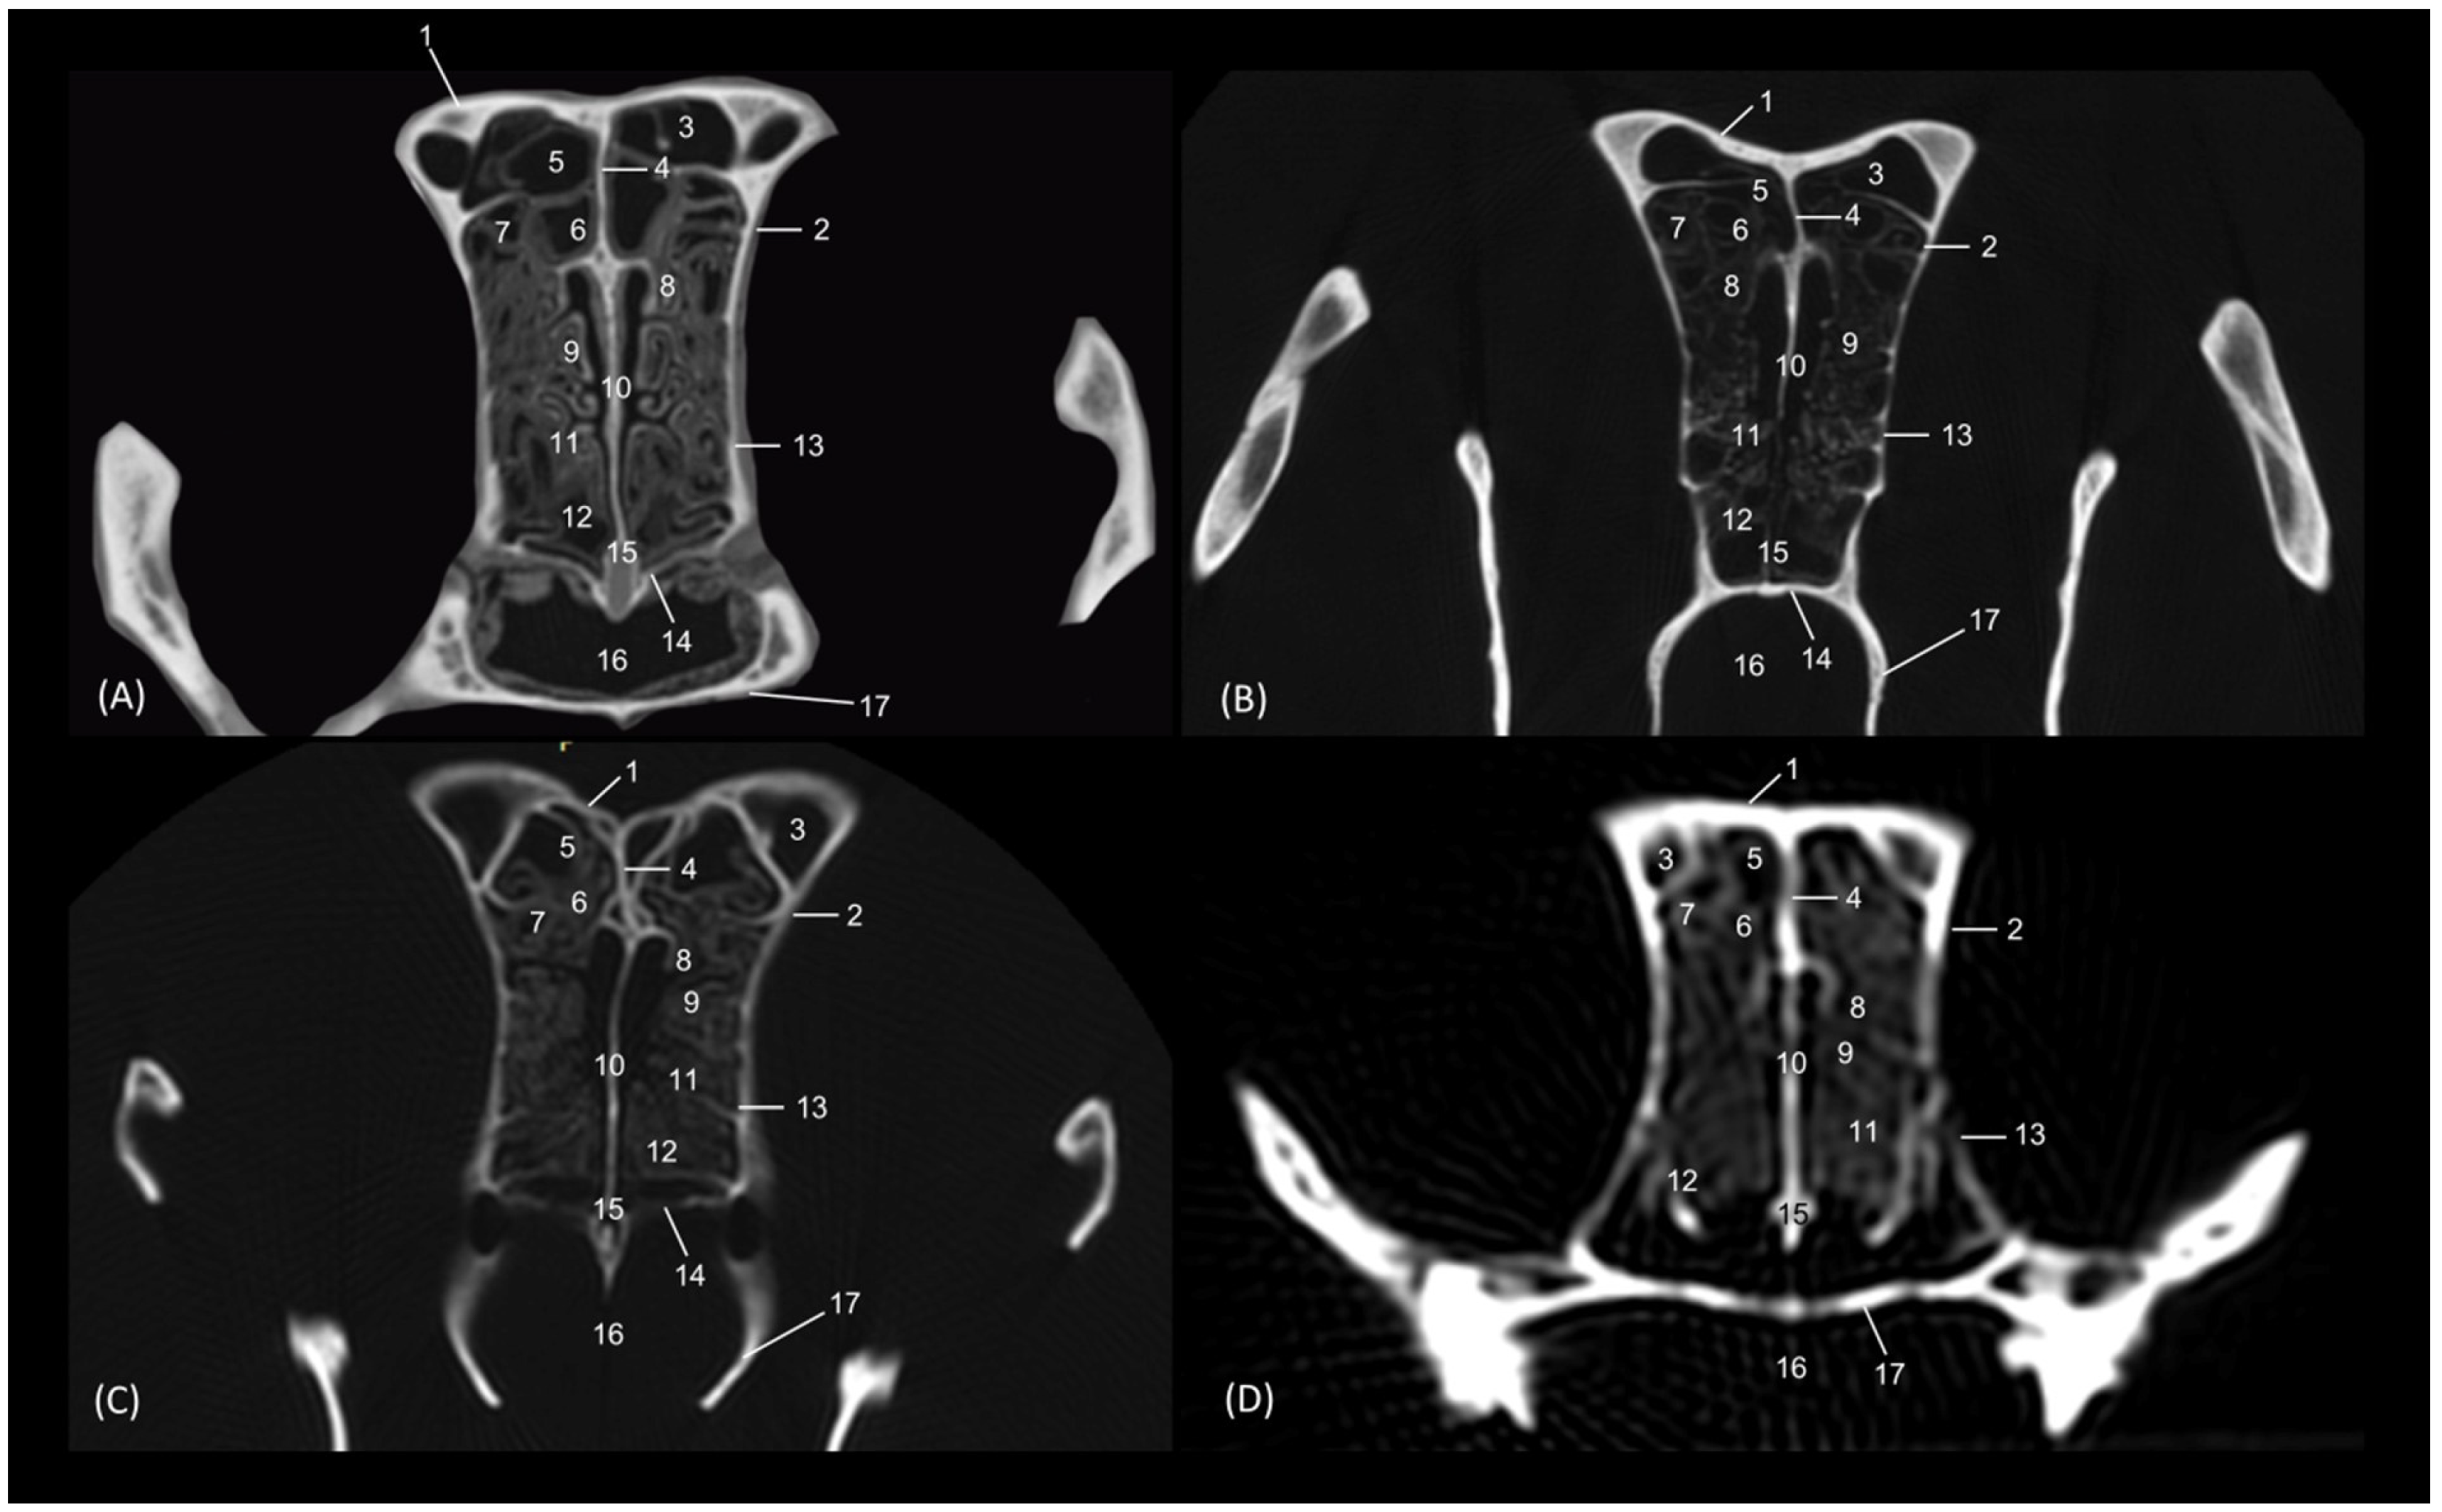

3.4. Felid Skulls CT

The section levels of each plane are represented in Figure 19. The CT study of the felid skull allowed for the identification in the three spatial anatomical planes of the bony base that makes up this cavity: transverse, sagittal and dorsal (Figure 20, Figure 21, Figure 22, Figure 23, Figure 24, Figure 25 and Figure 26). This study has been carried out on the leopard, the lion, the cheetah and the cat.

In a more caudal cross-section, the frontal sinus is visible in the leopard and the cat (Figure 21A,D), but not in the lion or the cheetah. The development of the middle and ventral nasal conchae could already be seen, as well as the great development of the third endoturbinate. Lateral to the ventral nasal concha, the maxillary recess could be identified. The infraorbital foramen was clearly observed at this level in all four species.

Figure 21. Amira representative transverse CT images at level of the middle portion of the respiratory part, level II. Images are oriented so that the left side of the head is to the right and the dorsal is at the top. All views are rostral. (A): Leopard; (B): Lion; (C): Cheetah and (D): Cat. 1. Nasal bone; 2. Frontal bone; 3. Maxilla; 4. Zygomatic bone; 5. Infraorbital canal; 6. Ethmoid bone: tectorial plate; 7. Maxilla: palatine process; 8. Nasal septum; 9. Vomer; 10. Dorsal nasal concha; 11. Middle nasal concha; 12. Ventral nasal concha; 13. 3rd endoturbinate; 14. Maxillary recess; 15. Frontal sinus; 16. Dorsal nasal meatus; 17. Common nasal meatus; 18. Ventral nasal meatus.

Figure 22 shows the greater thickness of the frontal bone and maxillae of the lion compared to the other species studied. At this level, the temporal process of the zygomatic bone is visible in all four species and the third endoturbinate reaches its greatest development. This was observed as a set of hyperattenuated lamellae on the medial part of the nasal cavity. The ventral nasal concha was already very small in all four species. Ectoturbinates were seen at this level only in the domestic cat. The frontal sinus was now apparent in the cheetah, but not yet in the lion. The tectorial plate of the ethmoid bone was seen as a hyperattenuated area at the base of the frontal sinus.

Figure 22. Amira representative transverse CT images at level of the middle portion of the respiratory part, level III. Images are oriented so that the left side of the head is to the right and the dorsal is at the top. All views are rostral. (A): Leopard; (B): Lion; (C): Cheetah and (D): Cat. 1. Frontal bone; 2. Maxilla; 3. Zygomatic process: body; 4. Zygomatic bone: temporal process; 5. Infraorbital canal; 6. Ethmoid bone: tectorial plate; 7. Maxilla: palatine process; 8. Nasal septum; 9. Vomer; 10. Dorsal nasal concha; 11. Middle nasal concha; 12. 3rd endoturbinate; 13. Ventral nasal concha; 14. Maxillary recess; 15. Frontal sinus; 16. 1st ectoturbinate; 17. 2nd ectoturbinate; 18. 3rd ectoturbinate; 19. Dorsal nasal meatus; 20. Common nasal meatus; 21. Ventral nasal meatus.

Animals 14 02609 g022

In the caudal section of the respiratory part of the nasal cavity (Figure 23), the frontal sinus could be observed in the four species. In it, the three ectoturbinates could also be identified as areas limited by hyperattenuated lines, the first and second being more medial and the third developing lateral to these. At this level, the ventral nasal concha could no longer be visualized. We observed that the body of the presphenoid bone closes the caudal wall of the nasal cavity. The space between it and the horizontal and perpendicular plates of the palatine bone forms the choana or the nasopharyngeal opening. The bony borders of the choanae could be seen in the leopard, while in the other species it was no longer ossified.

Figure 23. Amira representative transverse CT images at the level of the caudal portion of the respiratory part, level IV. Images are oriented so that the left side of the head is to the right and the dorsal is at the top. All views are rostral. (A): Leopard; (B): Lion; (C): Cheetah and (D): Cat. 1. Frontal bone: external plate; 2. Frontal bone: orbital surface; 3. Frontal sinus; 4. Frontal sinus: septum; 5. 1st ectoturbinate; 6. 2nd ectoturbinate; 7. 3rd ectoturbinate; 8. Dorsal nasal concha; 9. Middle nasal concha; 10; Ethmoid bone: perpendicular plate; 11. 3rd endoturbinate; 12. 4th endoturbinate; 13. Presphenoid bone: wing (orbital surface); 14. Presphenoid bone: body; 15. Vomer; 16. Choana; 17. Palatine bone: horizontal and perpendicular plates.